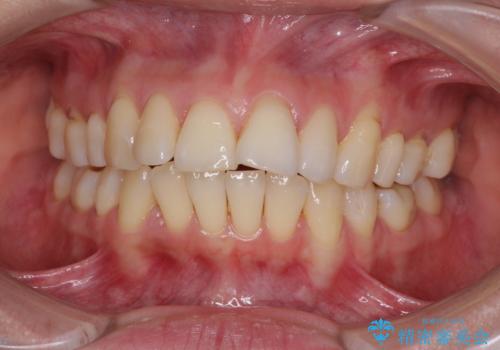

[ インビザライン矯正 ] マウスピースで治す前歯のがたつき

![[ インビザライン矯正 ] マウスピースで治す前歯のがたつきの症例 治療前](https://seimitsushinbi.jp/wp/wp-content/uploads/2023/11/C7-500x350.jpg?v=1699665009)